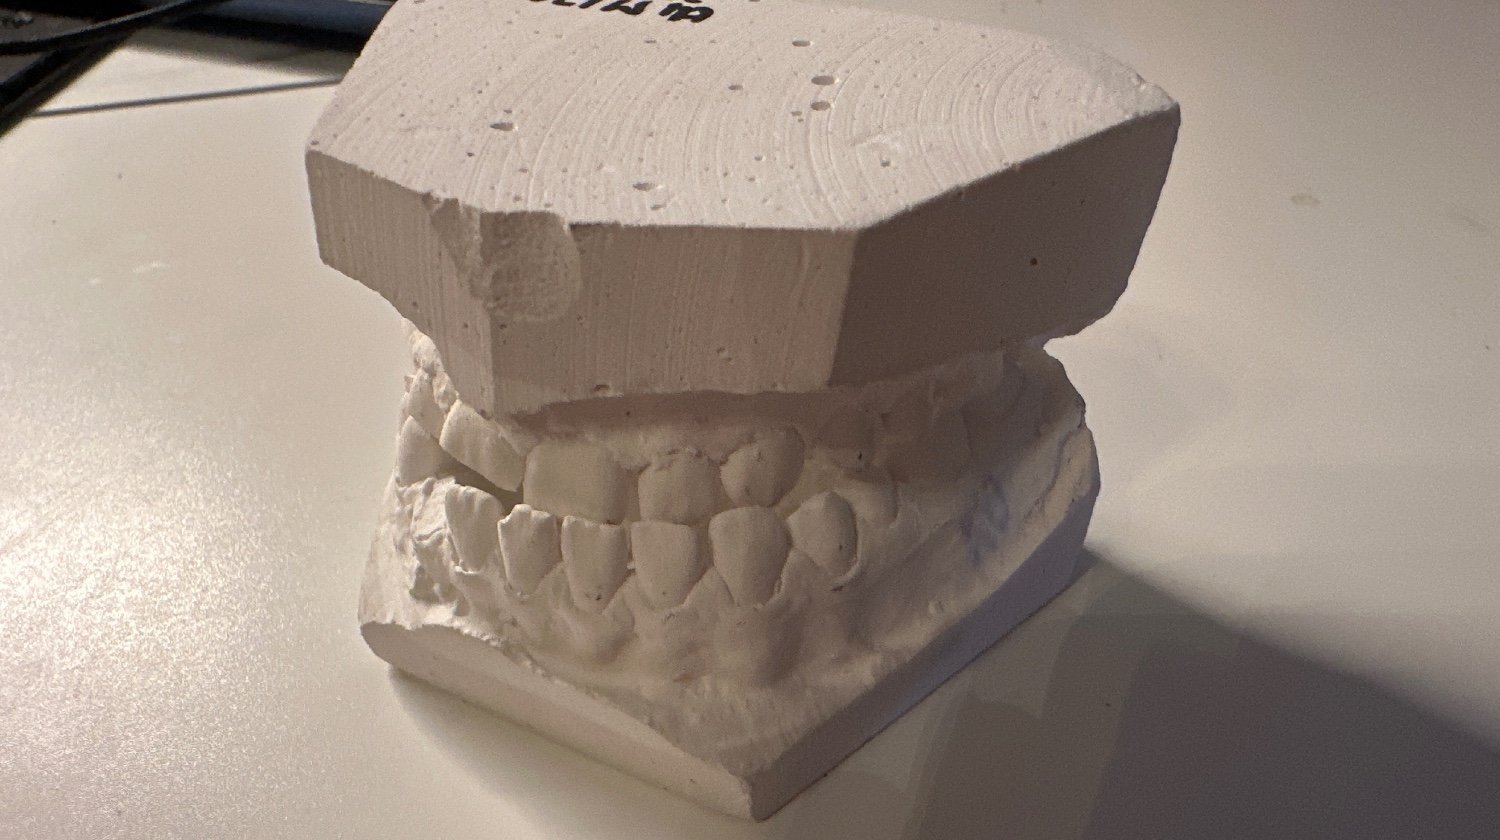

Mój aktualny stan zgryzu przed założeniem aparatu

Jestem aktualnie w trakcie zmiany ortodonty, który ma mnie przygotować do operacji. W pierwszej kolejności muszę wykonać badania, prześwietlenia takie jak np. pantonogram. Na zdjęciu zrzutki widnieje moje prześwietlenie z 2023 oraz 2021 roku. Przed i po usunięciu 8 do aparatu, którego założenie nigdy nie nastało. Niestety z czasem ulega ono przeterminowaniu i należy wykonać nowe. Jestem pod opieką ortodonty od już prawie 5 lat. Moje leczenie nie postępuje przez liczne przeszkody takie jak brak funduszy, problemy z ustaleniem operacji (w moim mieście tylko jeden chirurg operuje, który z dnia na dzień przestał operować) itp.

Po wykonaniu takiego zdjęcia należy zrobić wycisk zębów (stary wycisk widoczny na zdjęciach zrzutki), a następnie skonsultować plan leczenia z chirurgiem oraz ortodontą. W moim przypadku będzie to skrócenie i naprostowanie żuchwy oraz segmentacja górnej szczęki. Po jasnej decyzji chirurga ortodonta może założyć aparat, aby upośledzić zgryz (zgryz musi zostać upośledzony jeszcze bardziej, aby po operacji mógł zostać złożony prawidłowo). W między czasie dochodzą dodatkowe badania kontrolne wyciski, zdjęcia itp. Po ułożeniu zębów do operacji wyznaczany jest jej termin. Tutaj operacja jest na NFZ, jednak płytki do złączenia kości są już nie refundowane, a są one niezbędne. Jeśli wszystko po operacji dobrze pójdzie, pozostaje rekonwalescencja, konsultacje, badania kontrolne i rehabilitacja stawów. Po operacji noszenie aparatu może trwać jeszcze do 2 lat